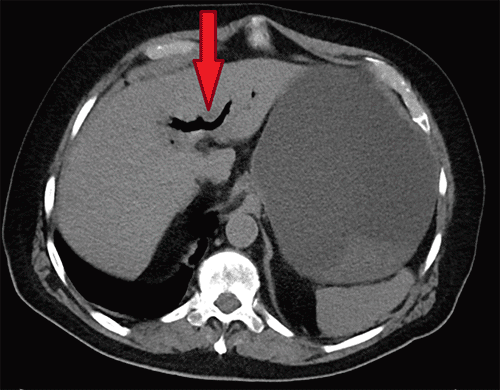

Figure 2. Axial CT Demonstrating Pneumobilia. Published with Permission

Non-contrast axial CT of the upper abdomen at the level of the liver. This image reveals branching, low-attenuation areas within the intrahepatic biliary tree (arrow), consistent with pneumobilia, secondary to a cholecystoenteric fistula

Upon initial evaluation, vital signs were: heart rate 108 beats/minute, blood pressure 123/74 mmHg, respiratory rate 18 breaths/minute, oxygen saturation 97% on 2 liters/minute supplemental oxygen via nasal cannula, and temperature 36.8°C (98.3°F). Pertinent laboratory findings included hypokalemia (3.1 mmol/L), hypochloremia (87 mmol/L), and acute kidney injury with creatinine of 2.97 mg/dL. Liver function tests showed a total bilirubin of 0.7 mg/dL and an alkaline phosphatase of 116 U/L. Sepsis workup revealed a markedly elevated lactate of 13.1 mmol/L and significant leukocytosis (17,800/uL). Physical examination demonstrated moderate abdominal distension with mild epigastric tenderness, without rebound tenderness or guarding. A non-contrast computed tomography (CT) scan of the abdomen and pelvis revealed significant gastric distension with copious intraluminal fluid, an ovoid foreign body measuring 8.3 cm × 3.7 cm × 3.6 cm impacted between the second and third portions of the duodenum, associated with surrounding duodenal pneumatosis (Figure 1). Pneumobilia was also evident (Figure 2). Following aggressive intravenous fluid resuscitation for acute renal failure and lactic acidosis, a nasogastric tube was inserted, yielding an immediate return of three liters of dark gastric fluid. His anticoagulation was reversed with prothrombin complex concentrate, and empiric broad-spectrum antimicrobial therapy with intravenous fluconazole 400 mg and piperacillin-tazobactam 2.25 g was administered. The patient was subsequently transferred to our tertiary care center for urgent hepato-pancreato-biliary surgical consultation.